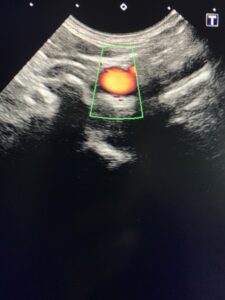

↑↑上の写真は、血管のようなチューブ状のものが見る方向によってどう見えるか?の例です。

←これが血管の横断面。

※わかりやすく、血管を赤く色づけしています。